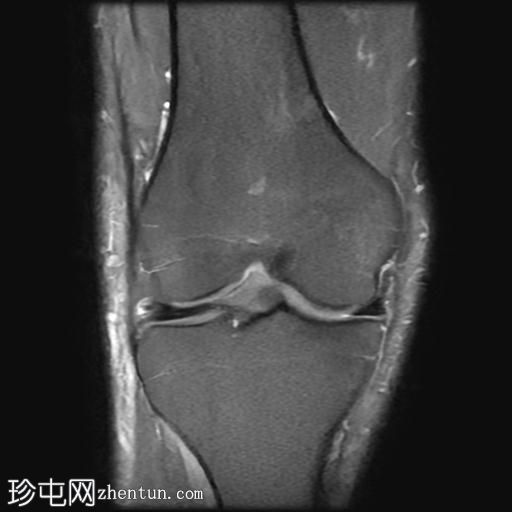

MRI

矢状位

T1加权像

T2加权像

PD脂肪抑制像

冠状位PD脂肪抑制像

轴位PD脂肪抑制像

髌骨前方可见一个卵圆形、充满液体的厚壁囊状物,伴有邻近皮下脂肪间隙水肿和脂肪条索影。

关节积液量极少。

内侧半月板体部及后角可见II级水平撕裂。

此外,外侧半月板体部可见局灶性放射状撕裂。

髌前滑囊炎是指髌前滑囊(位于髌骨与覆盖的皮下组织之间)的炎症和积液。